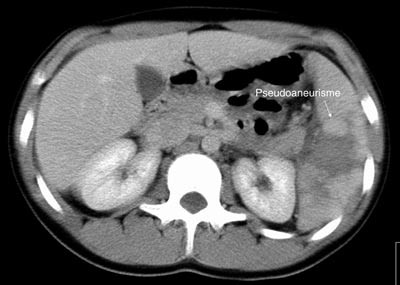

Pasient 1. En 16 år gammel gutt ble henvist til lokalsykehuset med spørsmål om miltskade. Han hadde seks dager tidligere falt under fotballtrening. Pasienten kom gående og klagde over magesmerter. CT-undersøkelse supplert med arteriell kontrastfase gav tydelig fremstilling av en rund, velavgrenset og høyattenuerende lesjon (fig 2a). På bildene fra vanlig venøs kontrastfase var denne strukturen dårligere fremstilt (fig 2b). Pseudoaneurisme ble mistenkt. Skaden ble vurdert som grad IV. Pasienten ble overflyttet til Ullevål universitetssykehus hvor det ble utført angiografi som bekreftet diagnosen. Deretter foretok man embolisering (fig 3). Prosedyren var vellykket og pasienten ble utskrevet etter én uke.

Pasient 2. En 20 år gammel mann ble utsatt for en trafikkulykke. Han var komatøs og ble intubert på skadestedet. CT-undersøkelse ved Ullevål universitetssykehus viste venstresidig pneumothorax og costafrakturer. I milten forelå en laserasjon kaudalt (skadegrad III), men normale funn i hilusnivå (e-fig 4). Pasienten ble observert og overflyttet til lokalsykehus etter tre dager. Seks dager etter traumet ble det gjort en CT-kontroll med arteriell kontrastfase. Denne viste en tilkommet, høytattenuerende lesjon ved milthilus, forenlig med et pseudoaneurisme (e-fig 5). Pasienten ble flyttet tilbake til Ullevål universitetssykehus hvor det ble utført angiografi med embolisering (e-fig 6). Ultralydkontroll samme dag viste opphørt sirkulasjon i lesjonen. Tre dager senere ble pasienten utskrevet.

I litteraturen er det beskrevet redusert sensitivitet og spesifisitet for pseudoaneurismer ved CT-undersøkelse sammenholdt med angiografi (8), men undersøkelsene er som oftest kun gjort i venøs kontrastfase. I flere studier er det benyttet forsinkelse fra kontrastinjeksjon til bildeopptak på mellom 70 og 85 sekunder som tilsvarer sen eller venøs kontrastfase (1, 9, 10). CT-bildene fra undersøkelsen av pasient 1 illustrerer at dette kan vanskeliggjøre diagnostikken. I tillegg er det viktig å vite at vaskulære lesjoner kan presentere seg forsinket. Det viser bildene av pasient 2. CT-undersøkelse i arteriell og venøs fase etter 5 – 7 dager i tillegg til undersøkelse ved innkomst er derfor anbefalt (2, 6).